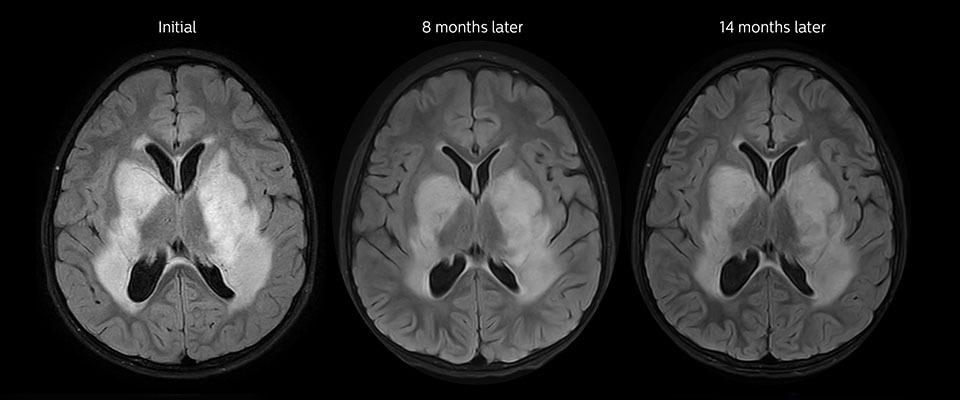

Low-grade glioma in a 5-year-old patient with neurofibromatosis 1. This low-grade lesion does not enhance on the post-contrast images, but does show an intermediate APT signal. The lesion stability over time confirms that it is a low-grade pathology.